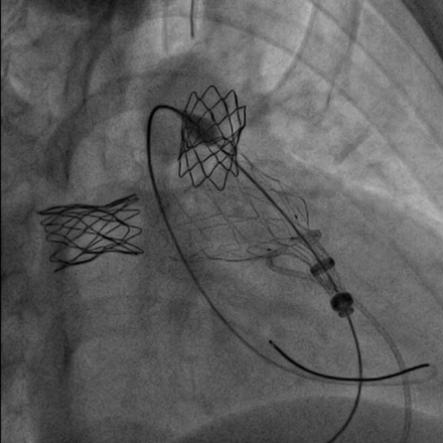

患者在全麻下,首先从左股静脉将造影导管分别送至右心室和肺动脉主干,行造影以明确右室流出道、肺动脉及肺动脉分支的基本情况。同时测量了右室流出道及肺动脉的尺寸。随后输送器通过右侧股静脉延加硬导丝将瓣膜输送到右室流出道,在X线的引导下,将瓣膜精确定位到植入部位并顺利进行瓣膜释放,无反流和瓣周漏,手术效果十分理想。